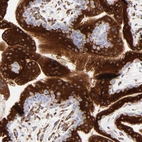

Immunohistochemistry analysis in human placenta and prostate tissues using Anti-C1QTNF6 antibody. Corresponding C1QTNF6 RNA-seq data are presented for the same tissues.